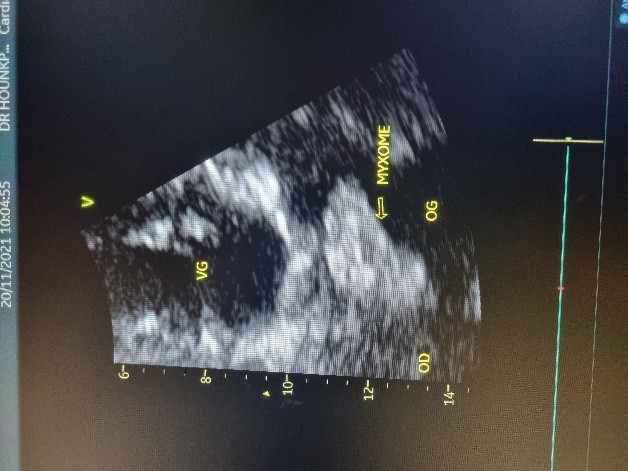

L’électrocardiogramme notait un rythme sinusal régulier avec une fréquence cardiaque à 83 bpm, des anomalies de la repolarisation en antéro septal à type d’ondes T biphasiques et en inférieur à type d’ondes T négatives asymétriques. La biologie était normale. L’échocardiographie (transthoracique et transœsophagienne) retrouvait les mêmes caractéristiques avec une masse appendue à la face atriale de la grande valve mitrale, obstruant partiellement l’orifice mitral et mesurant 49mm ×27 mm. Elle faisait protrusion dans le ventricule gauche en diastole (Figures 5 et 6). Cette masse était évocatrice d’un myxome de l’oreillette gauche. Le ventricule gauche n’était pas dilaté (DTDVG= 46mm), avec une fraction d’éjection systolique à 74% au Simpson biplan. Les pressions de remplissage du ventricule gauche étaient élevées. L’oreillette gauche était dilatée (VOG= 43mL/m²). Les cavités droites n’étaient pas dilatées. La fonction ventriculaire droite était normale (TAPSE= 24mm). On notait une hypertension pulmonaire avec PAPS =75mmHg, VmaxIT= 4,18 m/s. La veine cave inférieure était fine et compliante.

Figure 4 (a et b): Echocardiographie transoesophagienne en bi dimensionnelle, incidence 4 cavités plan oblique à 135° montrant un myxome appendu au septum inter atrial (Cas clinique n°2). VG= ventricule gauche ; OG= oreillette gauche ; VD= ventricule droit.